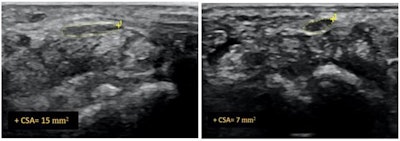

All three groups of patients showed a reduction in pain at the four-week mark. By the 12-week and six-month mark, both groups that received ultrasound-guided hydrodissection showed further improvement, while the group that received just a corticosteroid injection reported a recurrence of symptoms. In addition, follow-up ultrasounds showed a significant reduction of median nerve cross-sectional area in both hydrodissection groups, with group one demonstrating a reduction of 43% and group two of 46%. Group three showed only an 11% reduction.